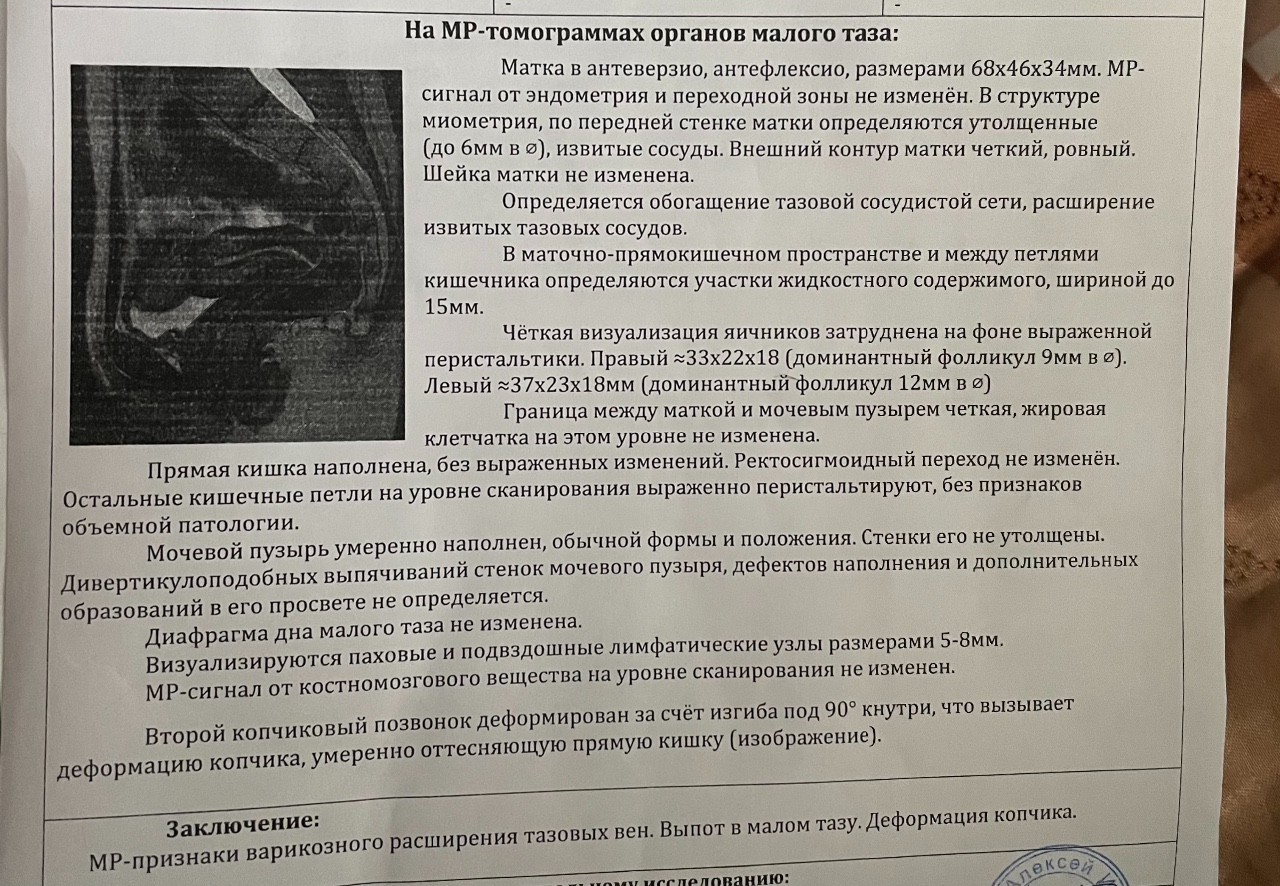

Магнитно-резонансная томография (МРТ) малого таза у женщин является важным методом диагностики различных заболеваний. На фотографиях МРТ можно увидеть органы малого таза, такие как матка, яичники, мочевой пузырь, прямая кишка и другие структуры.

Примеры фото МРТ малого таза у женщин

Ниже представлены примеры фотографий МРТ малого таза у женщин, позволяющие увидеть, как выглядят снимки и какие изменения могут быть обнаружены специалистами.